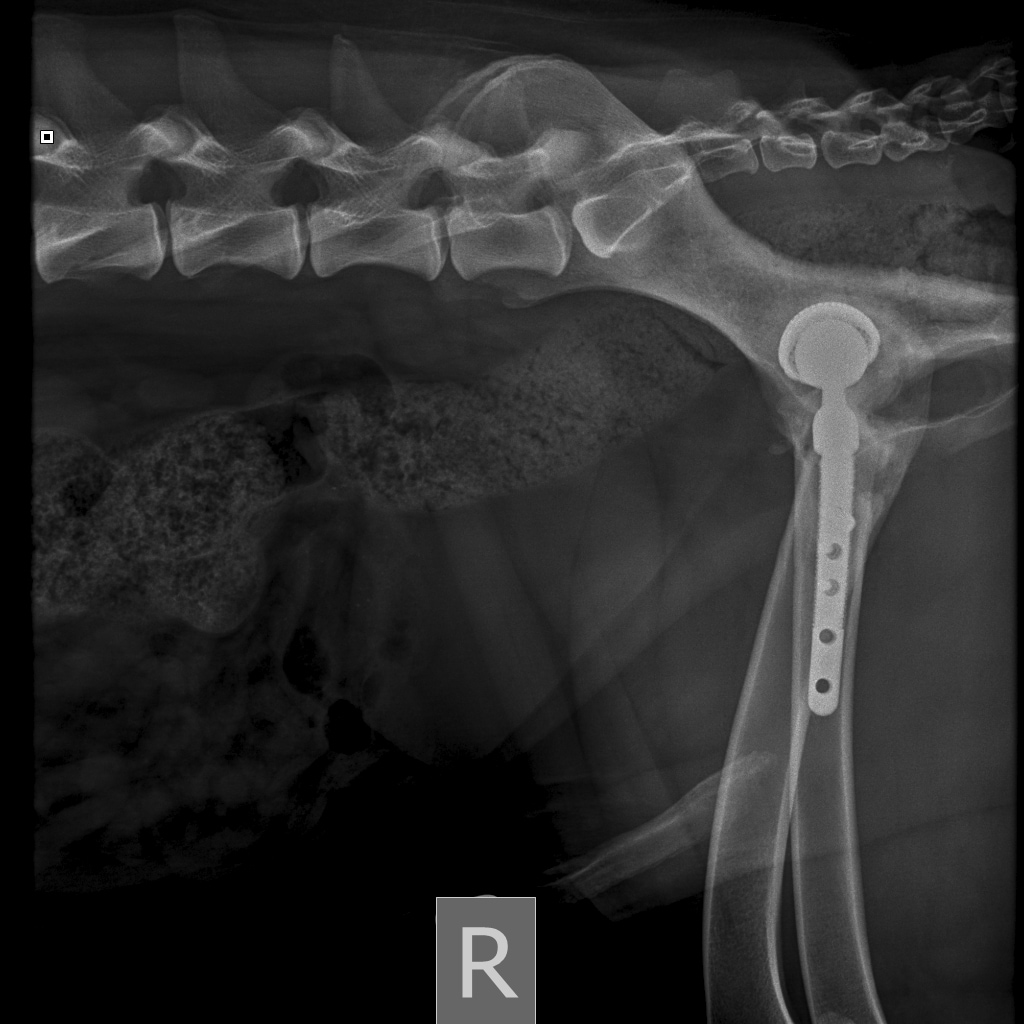

8A836050-66CA-42B2-94D3-F13B288A592B.jpeg

39B2671E-39B9-4502-9E11-ADB169612F24.jpeg

6950B9C9-79EA-4F34-A780-9C3C6BA31B49.jpeg

58C20B18-AA4E-4386-BF83-56CE5E282844.jpeg

Наш металлический мальчик

Железный дровосек